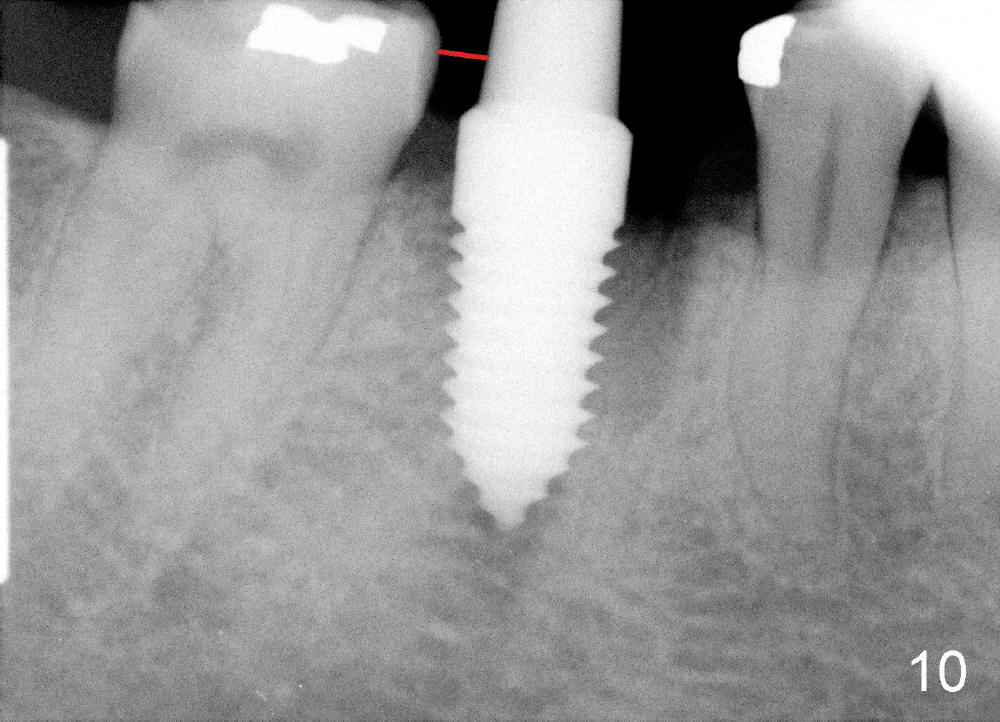

A 38-year-old lady agrees to have implant placement 7 years after loss of the crown of the lower right first molar (Fig.1,2). When the tooth is extracted, the septum is found to be low (Fig.3,4). To confirm it, a PA is taken (Fig.5). To initiate an osteotomy in the septum, it is trans-sectioned with thin osteotomes as shown in Fig.4 insert (black line). A 2 mm pilot drill is placed in the septum (Fig.6: P). The osteotomy is enlarged by 2.5-4.0 mm reamers (Fig.7,8), followed by insertion of 6x17 mm tapered tap at the depth 14 mm (Fig.9). The osteotomy is further enlarged by 4.5 and 5.0 mm reamers. A 6.0x14 mm one piece implant is placed initially. The trajectory is not ideal. A 6.0x14 mm one piece implant is placed initially. The trajectory is not ideal. The implant is removed from the osteotomy partially and reinserted with improved trajectory (Fig.11, compare to Fig.10 (red line)). Primary stability is high. There is not much bone mesiodistally so that the trajectory is easily changed in that direction. After abutment preparation, mixture of autogenous bone (harvested from reamers) and allograft is placed in the residual mesial and distal sockets (Fig.12). To contain the bone graft, an immediate provisional is placed (Fig.13 P). The occlusal plane of the provisional is significantly lower than that of the adjacent teeth to avoid micromovement of the implant. The patient is advised to eat soft food on the left side. Six days postop, the patient returns for prophy. The provisional is removed; the bone graft appears to be incorporating into the socket (Fig.14). After recementation, the provisional remains in place for 3.5 months; PA shows increased bone density in the mesial and distal sockets (Fig.15, compare to Fig.5,11). Due to insurance coverage, the patient defers fabrication of definitive restoration for at least 7 months. The immediate provisional is finally lost 8.5 months postop: the gingiva attaches to the 1-piece implant (Fig.16), while the density of the mesial socket increases (Fig.17 *) with formation of the cortex (lamina dura) coronally (v). Before the provisional (Fig.18 P) is removed for cementation of the definitive restoration, black shadow (*) is noted over the buccal gingiva. It is partially due to buccal placement (Fig.19) and partially due to buccal atrophy over a period of 10.5 months postop. How to prevent buccal placement? Positioning the first pilot drill in the septum buccolingually is a key. Eleven months post crown (Fig.20 C) cementation, the black shadow remains, but there is no tenderness. If the implant threads are immediately underneath the periosteum, there is tenderness.